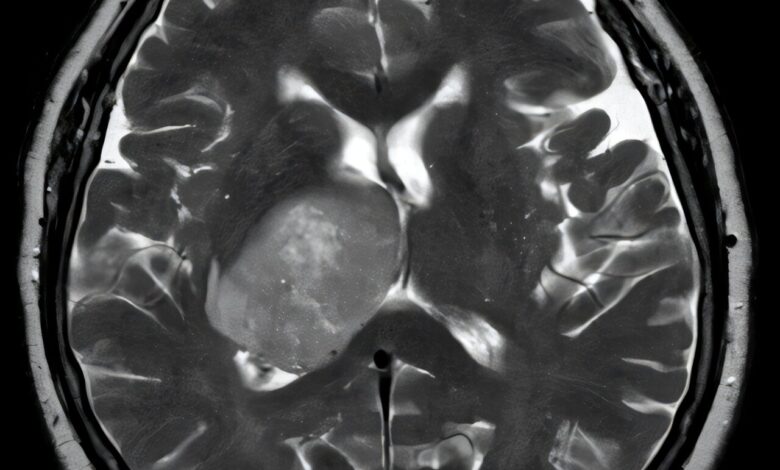

Nástroj nazývaný obrázek (nástroj pro charakterizaci obrazu patologie s rychlými hodnoceními nejistoty), rozlišující s téměř dokonalou přesností mezi glioblastomem-nejběžnějším a nejběžnějším a nejběžnějším a nejběžnějším a nejběžnějším a Agresivní mozkový nádor—A a primárního lymfomu centrálního nervového systému (PCNSL), vzácnější rakovina, která se často mýlí s glioblastomem. Zatímco oba se mohou objevit v mozku, vzniká glioblastom mozkové buňkyzatímco PCNSL se vyvíjí z imunitních buněk. Jejich podobnosti pod mikroskopem často vedou k nesprávné diagnóze s vážnými důsledky pro léčbu.

Správná identifikace nádorů podobných vzhledům v mozku během chirurgického zákroku je jednou z nejtěžších diagnostických výzev v neuro-onkologii, uvedli vědci. Přesná diagnóza, zatímco pacient je stále v operačním sále, může pomoci urychlit výběr kritických léčby, jako je to, zda má provozovat a odstranit rakovinnou tkáň – jak by mělo být provedeno s glioblastomem – nebo ji nechat za sebou a rozhodnout se místo toho pro radiaci a chemoterapii, preferovanou terapii pro PCNSL. Nepřesná nebo zpožděná diagnostika rakoviny v mozku může vést k zbytečné chirurgii a zpoždění při správné léčbě.

Přesné rozlišování PCNSL od glioblastomu během chirurgického zákroku by mohlo chirurgům umožnit ušetření mozkové tkáně místo toho, aby ji odstranily. Pacienti s PCNSL jsou poté odkazováni na záření a chemoterapii, což je preferovaná léčba tohoto typu nádoru. Naproti tomu glioblastom vyžaduje chirurgické odstranění co nejvíce rakovinné mozkové tkáně.

V testech obraz obrazového modelu správně rozlišoval glioblastom od PCNSL více než 98% času – úroveň přesnosti, která se držela při testování v pěti nezávislých mezinárodních skupinách pacientů. Kromě toho obrázek identifikoval vzorky patřící k 67 CNS rakovinám, které nebyly ani gliomy, ani lymfomy.